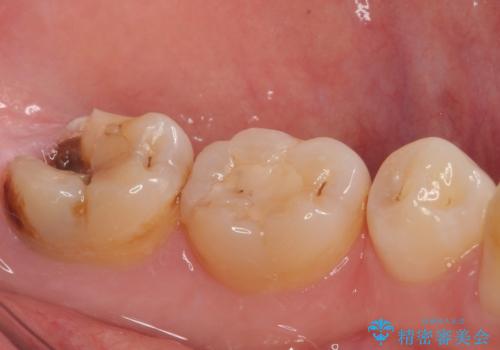

左下の虫歯が歯茎の下にも広がっているので、歯茎の位置を下げるためディスタルウェッジを行い埋伏親知らず抜歯を行いました。また同日に左下の歯を仮歯に変えています。